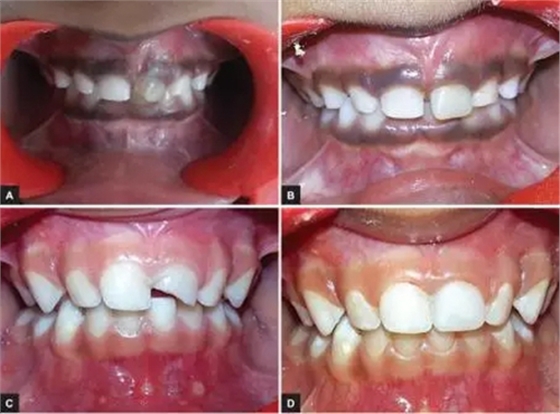

本研究中,其他患齲齒或牙外傷的患兒均采用此方法使用臨時(shí)冠材料進(jìn)行美學(xué)修復(fù),下圖分別為兩例乳前牙齲齒(圖2)和兩例牙外傷(圖3)的病例。

圖3.(3-A,3-B為乳前牙外傷病例1 3-C,3-D為乳前牙外傷病例2)